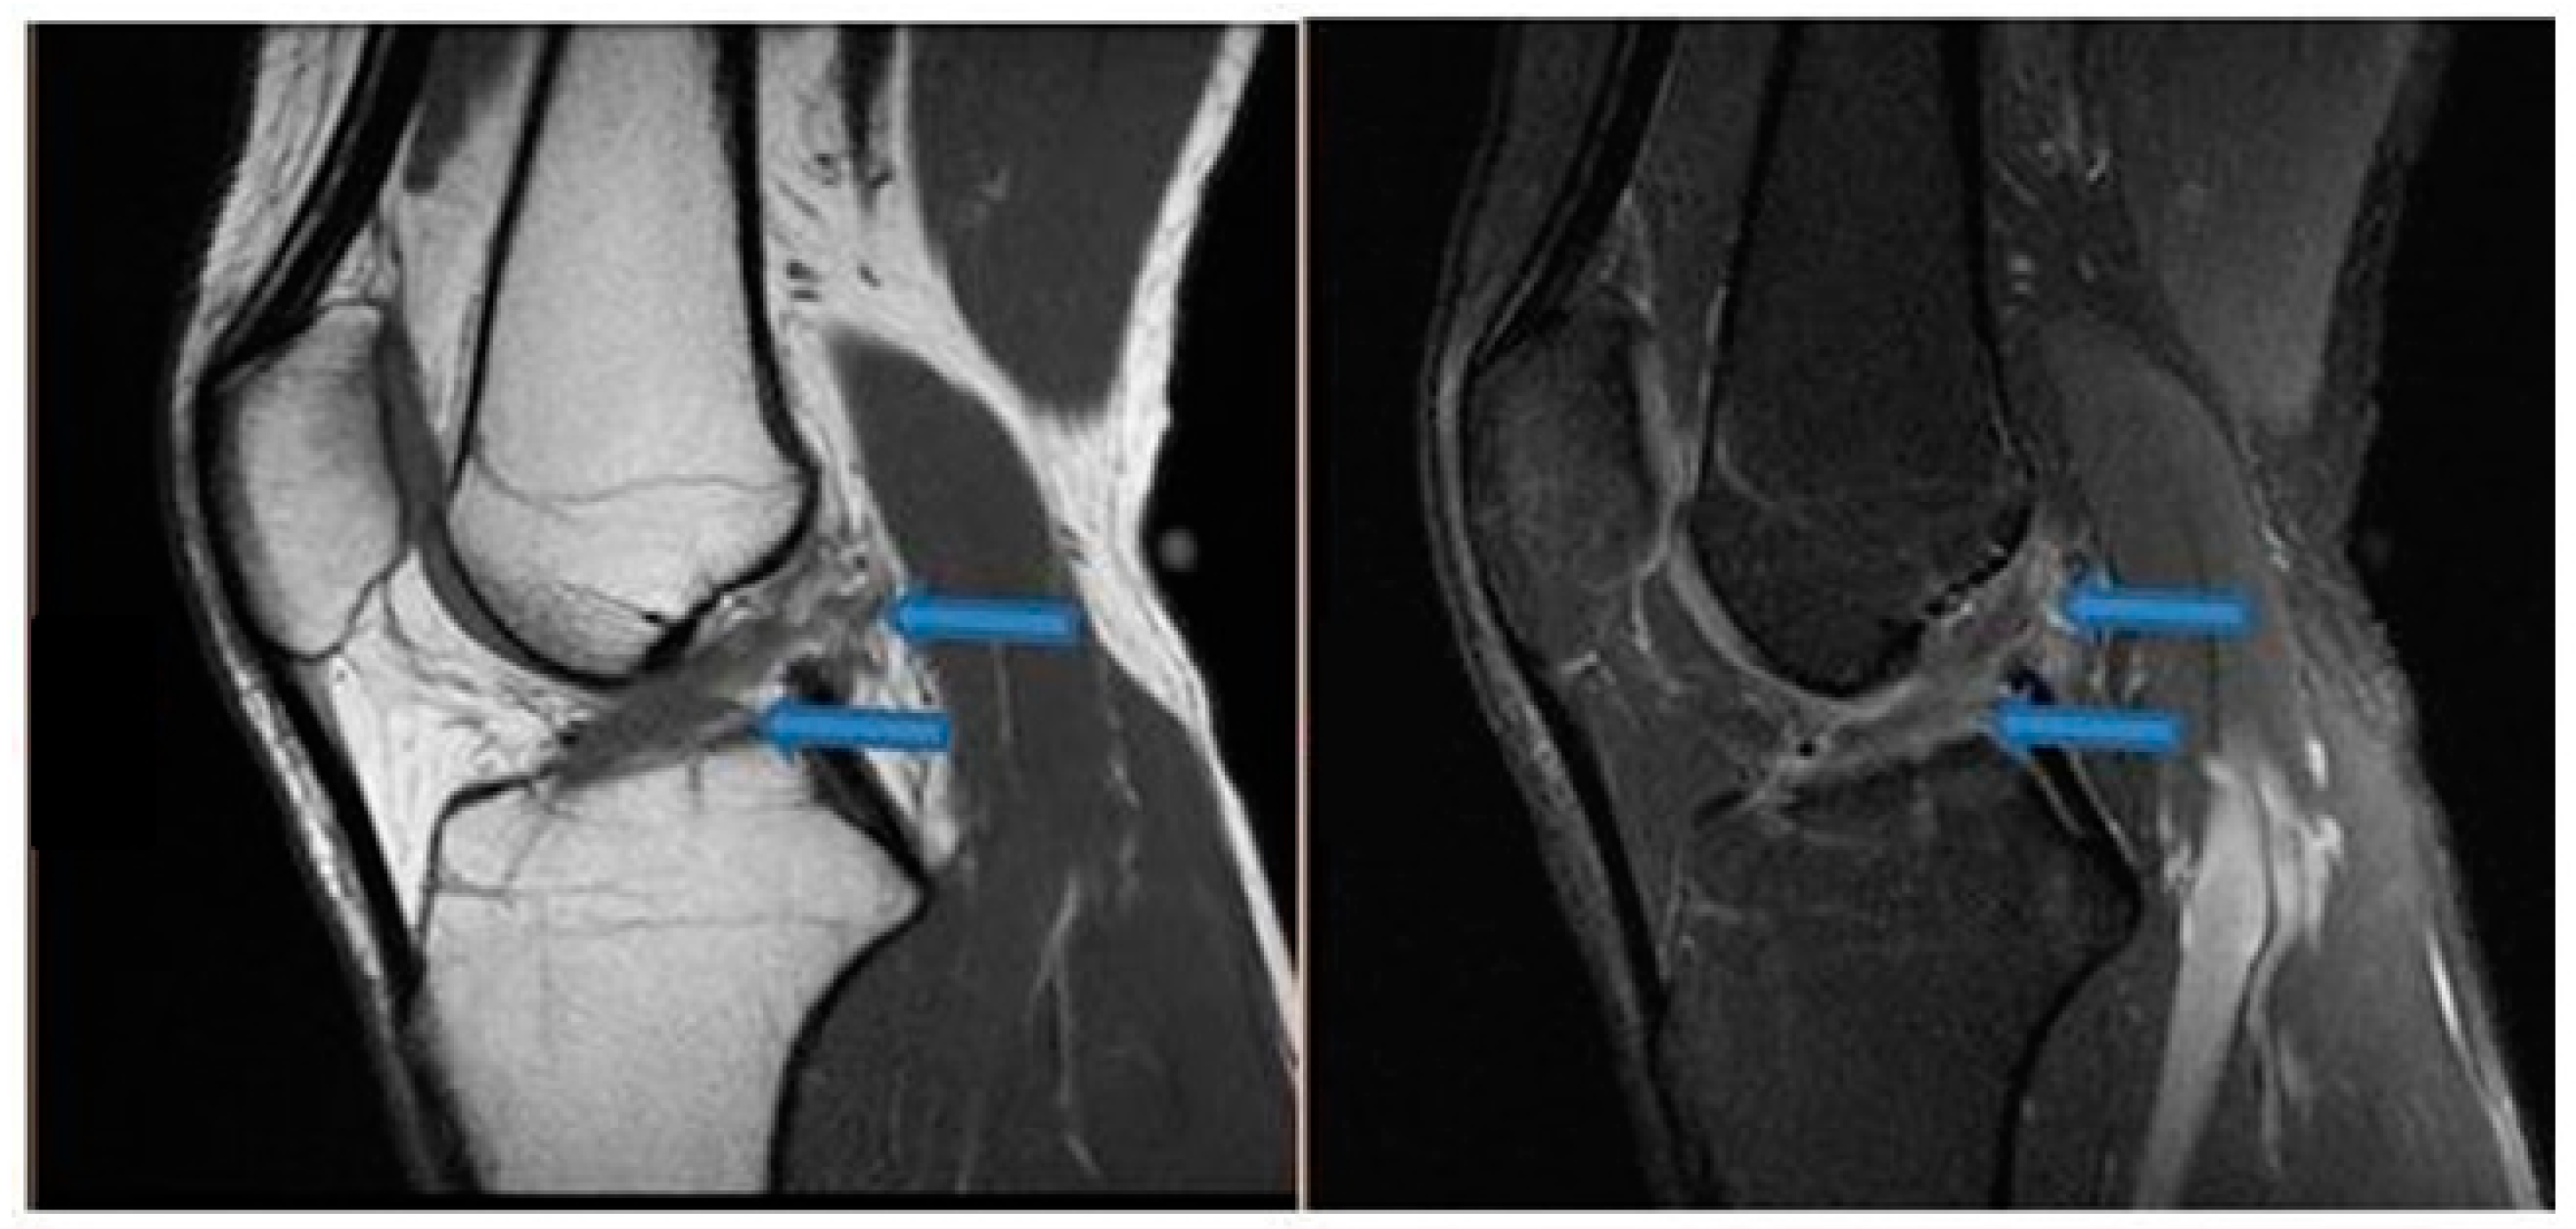

| 9 November 2020 | MRI scans demonstrating signs of partial ACL healing |